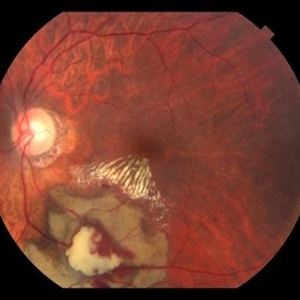

Photo of Large Hemorrhage with macular detachment due to AMD

Nov 7 2019 by John S. King, MD

81-year-old white female with three day history of seeing a "dark blob" nasally OD; no blood thinners; vision was 20/100- J16 with 2+NSC OD; OCT (not shown) had large SRF that included the fovea and extended out temporally. Posterior segment showed a large amount of SRF in the macula with some SRH in the inferior portion of the macula, hemorrhagic PEDs temporally with some RPE scarring and SRH in the periphery. On the FA there is blockage by the SRH and SRPE heme; there is staining peripherally; there is a wavbe of leakage that extends out into the macula and pools into to subretinal space. Anti-VEGF given; f/u one month.

Photographer: Brandon Peter

Condition/keywords: retinal pigment epithelium, subretinal hemorrhage, wet age-related macular degeneration (wet AMD)